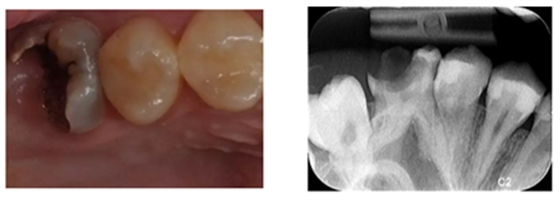

检查:26冠部大面积龋损,仅余近中颊侧残壁,残余牙体颜色变暗,牙龈增生至缺损牙体组织内部,髓腔内炎性牙髓组织增生呈息肉状。探诊(+),冷诊(±),叩诊(-),无松动。

X-ray示:26远中低密度影已穿通髓腔,与近中低密度影几近相连。根尖无低密度影像。

诊断:26慢性牙髓炎